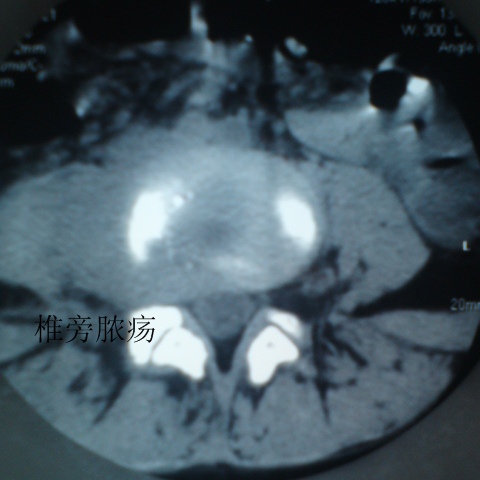

标题: CT27836:女 ,13岁,腰痛数月,加重一月,检查下腰部明显压 [打印本页]

标题: CT27836:女 ,13岁,腰痛数月,加重一月,检查下腰部明显压

考虑腰4椎体结核伴右侧椎旁及椎管右侧硬脊膜外脓肿形成。

以下是引用liaoqiang在2010-7-21 12:39:00的发言:[br]考虑腰4椎体结核伴右侧椎旁及椎管右侧硬脊膜外脓肿形成。

考虑腰椎结核伴右侧椎旁及椎管右侧硬脊膜外寒性脓肿形成;建议必要时行mri检查。